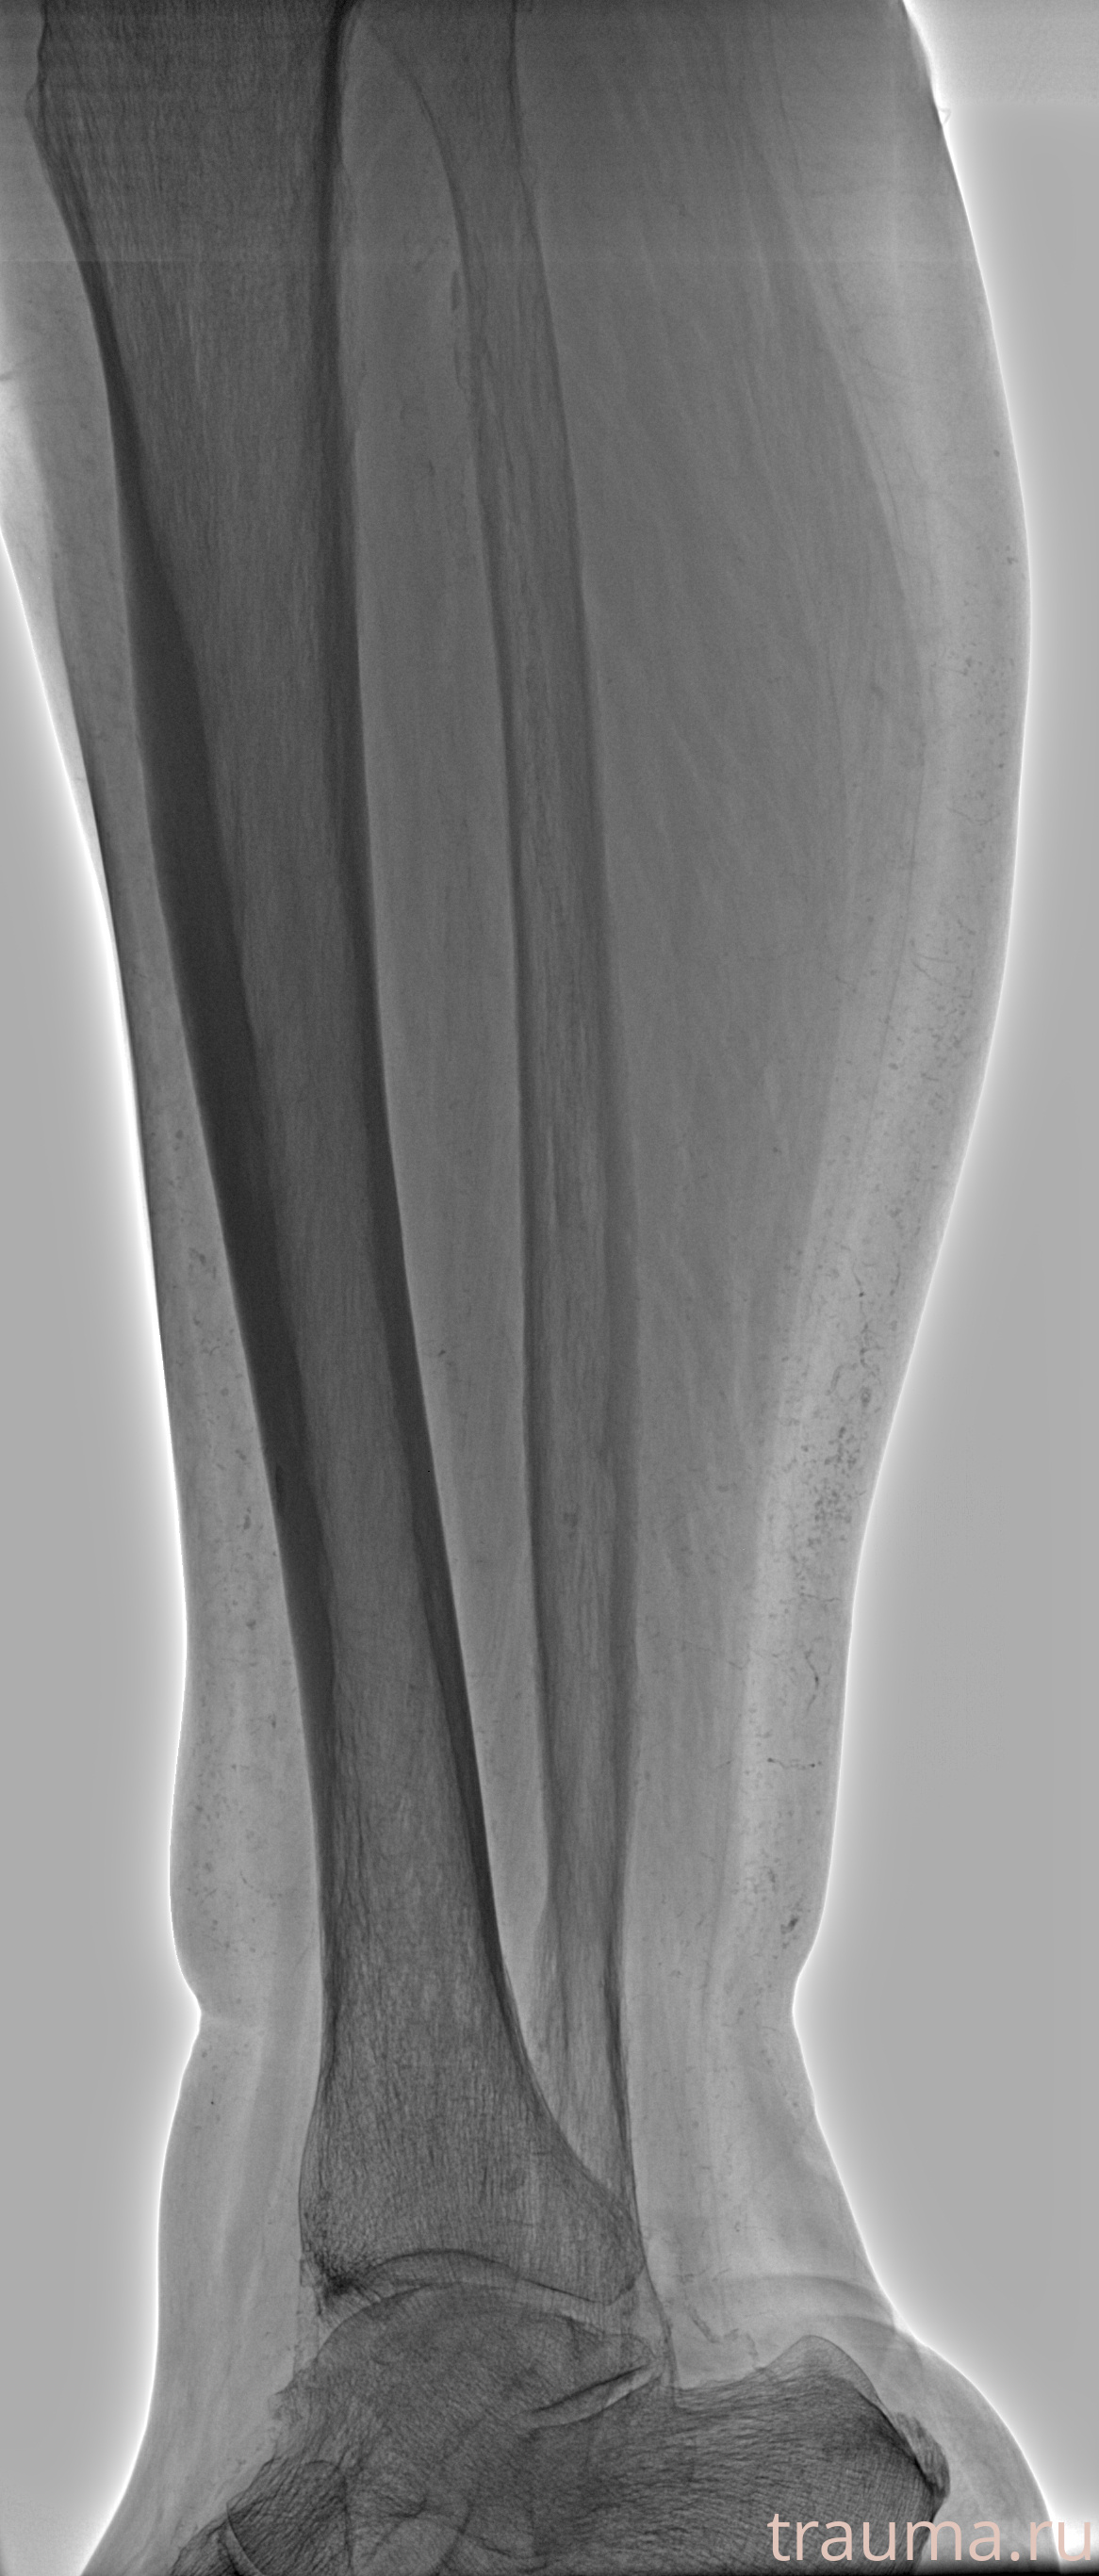

Рентгенограммы

Рентген на дому: по вашему адресу приезжает врач-рентгенолог, травматолог-ортопед с мобильным рентгеновским аппаратом, проводит диагностику травмы или заболевания, делает необходимые рентгенограммы, дает рекомендации по дальнейшему лечению. Получить качественные снимки в домашних условиях возможно благодаря уникальной методике, разработанной МосРентген Центром для института  Склифосовского